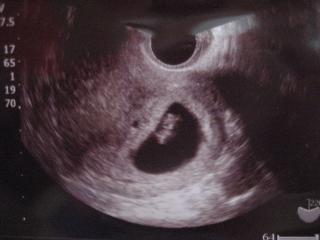

こんにちわ~ずっと雨でやっと晴れたと思ったら暑くなりましたね今日は布団もカバーも思いっきり洗って干しました!掃除もしていらない靴も捨て朝から気分スッキリで、赤ちゃんどうなってるか・・・考えてもわかるはずないいし実感ないし産婦人科、行くとお金かかるなぁ・・・でもあんまりすぐ行っても前と変わらなかったら意味ないしお腹の赤ちゃんは無事いてくれてるのか育ってなかったらたらどうしよう・・・と2週間と2日あれこれ考えてましたよ旦那も心配してました(出血と強いお腹の痛みがあったからね)旦那は仕事なので暑い日ざしの中、一人自転車こぎこぎ産婦人科へ今日は午前診のみだったせいか患者だらけで1時間以上待ちました…o(;-_-;)oドキドキ♪ジャーン(写真をカメラで撮ったので光入りまくりでスミマセン)この前の「袋」が大きくなりその中に小さな生命体が入ってます産婦人科も混み合ってて、診察室2つで名前も確かめられず入り似たような体系の妊婦さんも一緒にいたけど写真、間違ってないよねとの疑問点はありますが、8週とのことです(*'-^*)bぶいっ♪最終生理日から周期を計算してるせいか、33歳という年齢の為育ちにくいせいか8週にしては【小さめ】らしいですが 強制的に採血(するものなの?!)して本日13200円なり産婦人科から戻り、自営してる旦那に報告に行くとすでに仁王立ちwホッとひとまずは安心と共にシッカリしなきゃと彼なりに思ってるのでしょうね(o^∇^o)産婦人科行く前に母子手帳もいただきましたしまだ実感なんてないですが、育っててよかったです先生に確認したところ仕事しても問題なしとの返事でしたので8月からアルバイト(自営だけでは苦しいのでわずかながら稼いでます)も再開しようと思ってます。

こんにちわ~おひさしぶりです長いことブログの更新してなかったハムタですが妊娠しました(*^。^*)今まで子供つくる余裕ない、ないとここまできてとうとう33さい。。。そろそろ種付け(?!)にかからないと高齢出産にかかるぞってなことで子作りを開始したわけですが・・・一っ発命中~~~!!そんな簡単にいくわけないと思ってたので、絶対生理あると思ってた・・・あれちょっと遅れてるかな(いつも乱れないハムタですが)と7/2に妊娠検査薬をしてみたうは~うっすら陽性だったのですよ!!おそるべし旦那の精子Σ(`д`ノ)ノ (実はH自体1ヶ月1,2回しかしない淡白な夫婦で、この前も1ヶ月ぐらい空いてたから旦那の精子死んでるだろうとおもってた・・・(汗)ちなみに検査薬にかかってる液体、濡れた手で触ったのかな?たぶん水ですw(キャップ部分だし)7/2(木)に検査薬して仕事が休みの7/6(月)に産婦人科行きました出かける前にトイレ行ってて、受付で「尿採ってください」と出るもんだねちょぴっとだけれど…o(;-_-;)oドキドキしながら(時間が長く感じる)待ってやっと番がきて診察先生と少し話し、診察台へ(うぎゃ~~~き、きたか)変な温かい器具を体の中心部へ挿入すること3回もっと抜き差しは優しくしないと痛いっちゅうねん(泣) 妊娠5週との診断なにがなんだかわからないグロい画像ですみません(のでちょっと小さくしました)中央左に映ってる黒い丸いのが赤ちゃんが入る袋です♪もうしばらくするとこの黒い袋の中に赤ちゃんが見えるのです先生とまた少しお話してお会計へ・・・・5000円なり(T.T)実は次の日仕事で無理しすぎて(手抜きは出来ない性格)生理始まるみたいな出血があり(調べてみたらこの時期が一番流産の可能性が高いのね・・・)でその夜ものすごいお腹のハリと痛みで「流産するかも」とこの小さな命を大事にしてやれなかった悔しさで涙が出ました旦那と相談してというか旦那が仕事辞めれ!というので早速次の日職場に行き決まってるシフトを交代してもらい、店長に安静の為しばらく休むことを伝えました(仕事続けるかどうかはまだ未定ですが)安静にしてたのがよかったのか出血も3,4日でおさまりつわりのような胸のムカムカも1週間もしないで通り過ぎました(早くない)無事生まれてくるかはまだまだわからないけれど、今はただ、無事でいて欲しいと願うばかりです・・・そして私の栄養はベビーの為にってことで毎日1本ずつ続けようと思いポチっ トマトジュース&野菜ジュース30本で1310円、送料90本まで一緒だから大量購入しましたv( ̄ー ̄)v届くのが楽しみだなあ